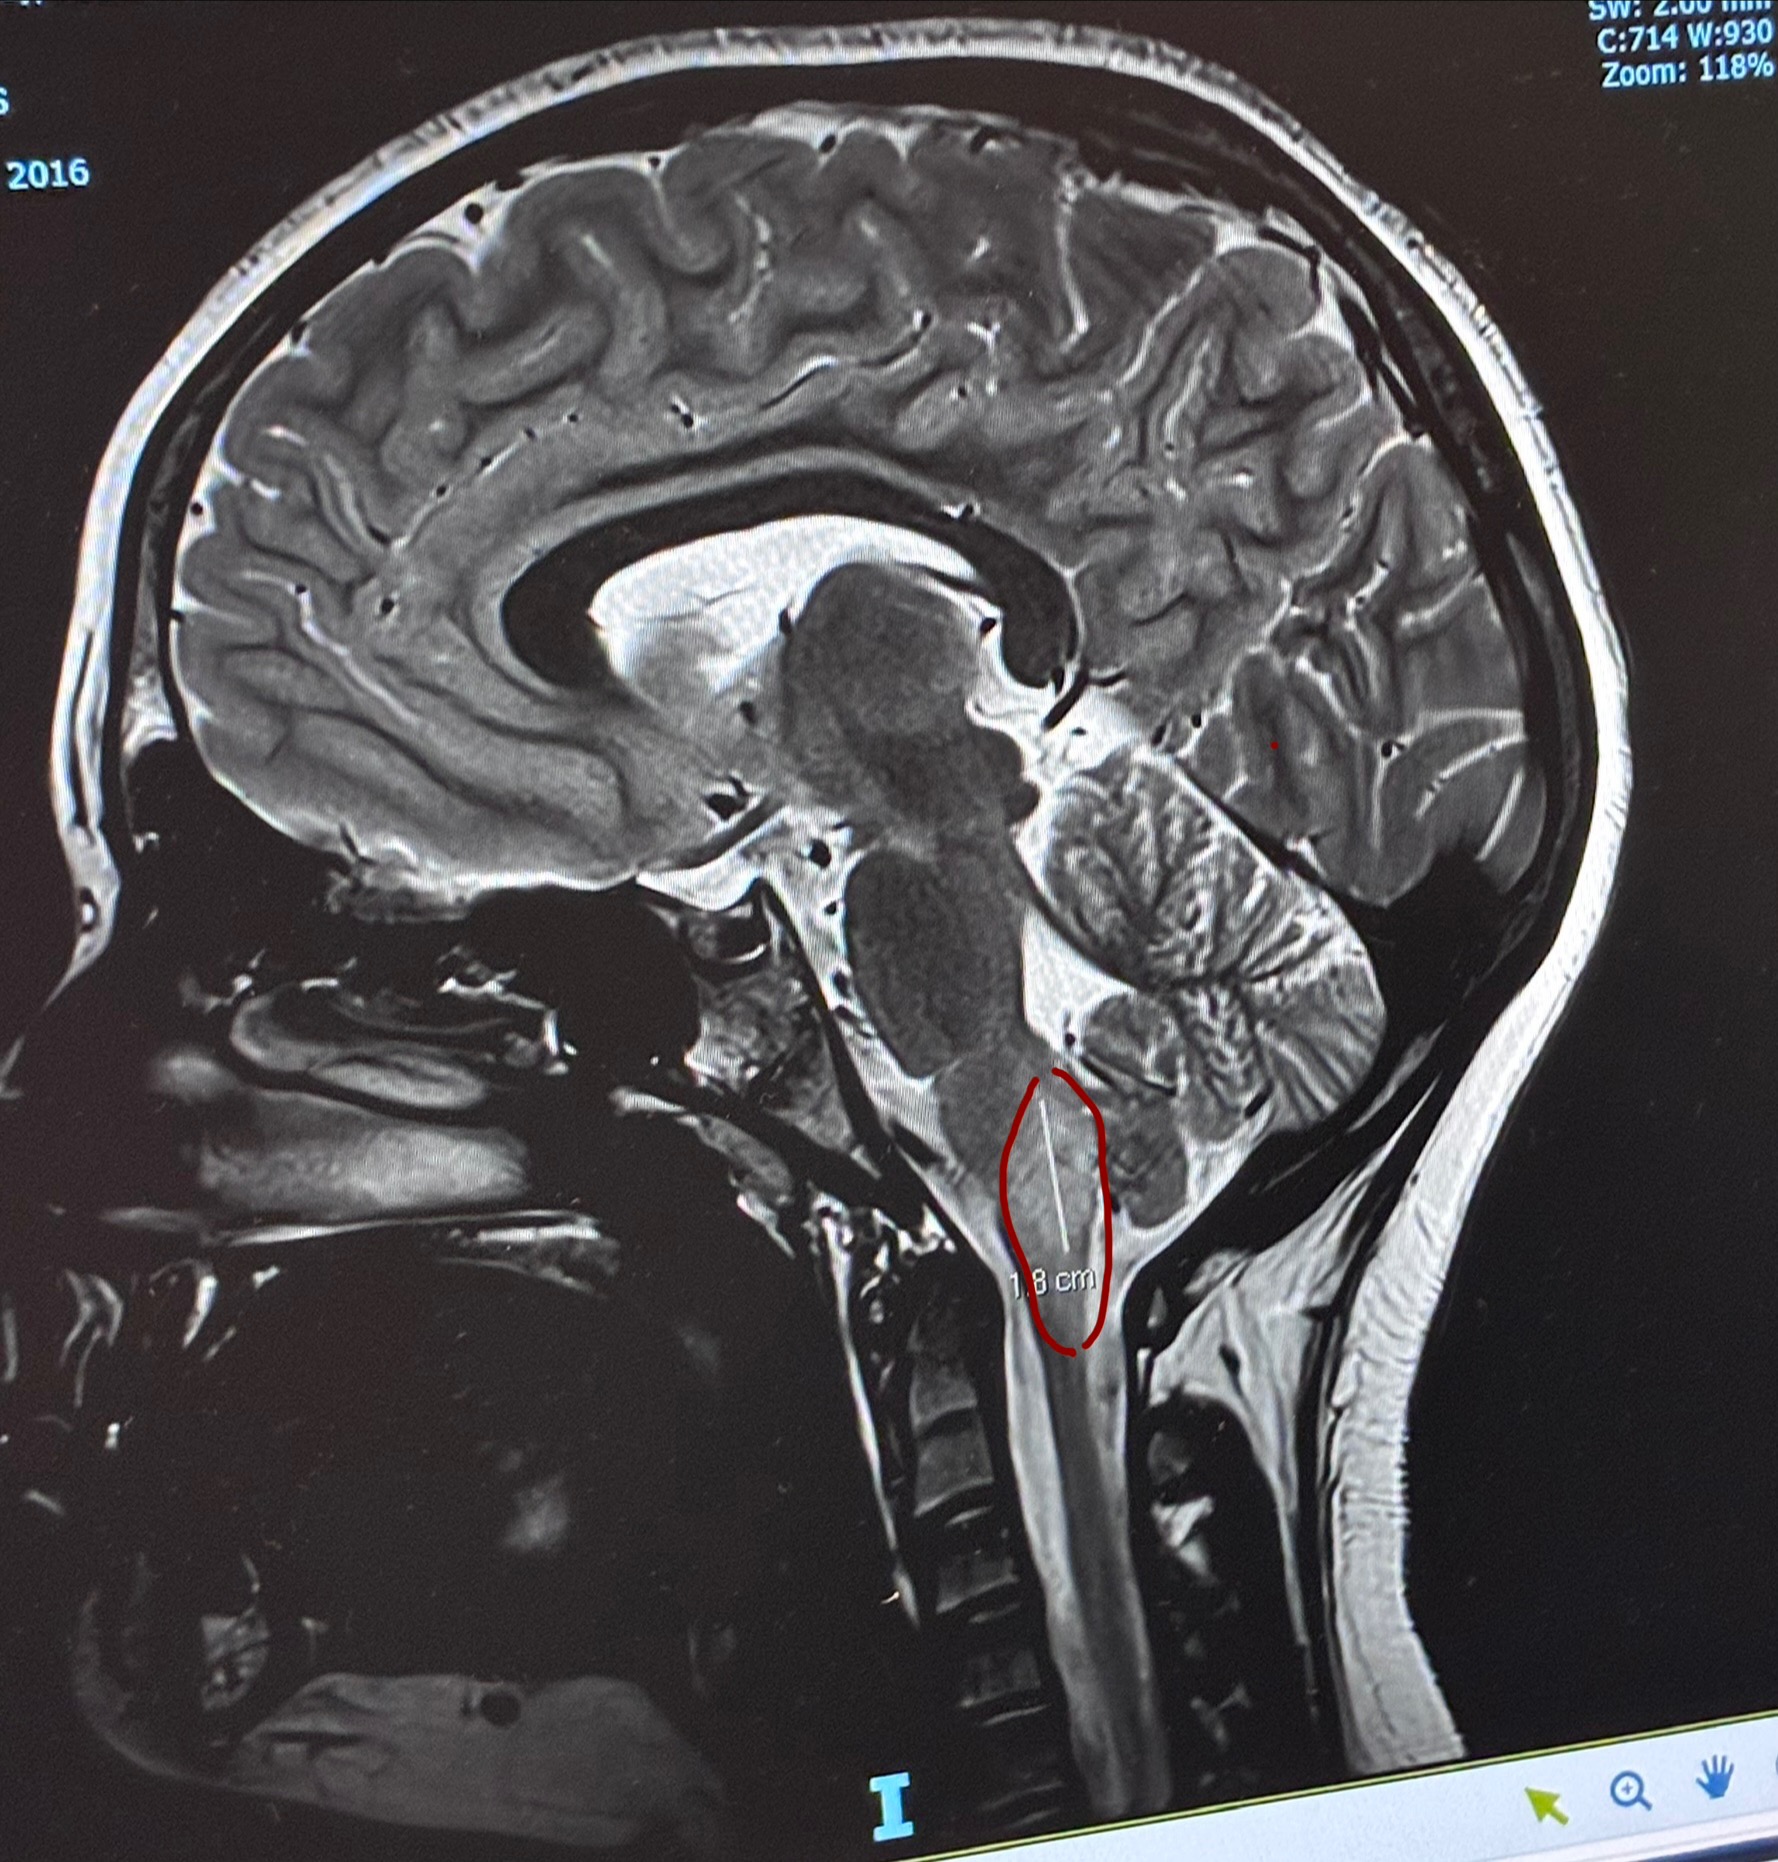

Zahlee is 9 years old and has been battling illness and disease her whole life. When she was 3, an MRI discovered a lesion on her brainstem, which we now know is a Low Grade Glioma.

Recently, Zahlee has shown some decline again. MRI revealed that the tumour has had further growth and now she will need to begin a gruelling 18 months of weekly chemotherapy.